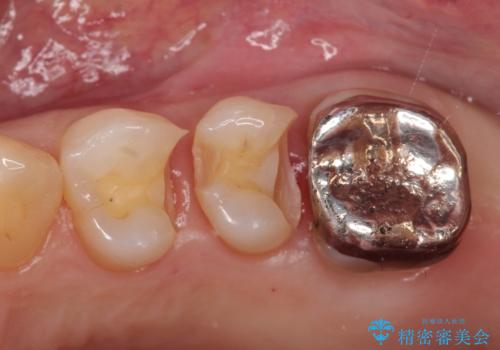

- 左上の4番目と5番目の歯(小臼歯)に入っている銀歯を白くしたいという主訴でご来院されました。

診査の結果、長年使用されていたメタルインレーは経年劣化により適合が悪くなっており、金属の溶け出しによる歯肉の変色や、内部での虫歯再発のリスクも懸念される状態でした。そこで、金属を一切使用しないメタルフリー治療として、耐久性と審美性に優れたセラミックインレーへのやりかえをご提案しました。

治療ではまず、古いメタルインレーを慎重に除去し、内部のわずかな虫歯を取り除いてから形を整えました。